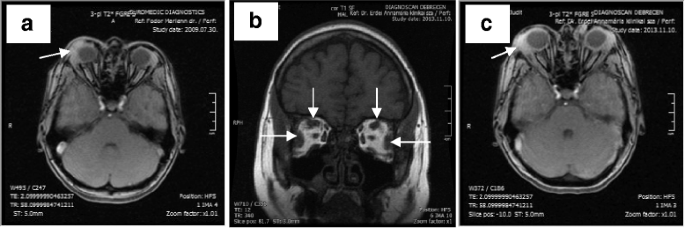

The patient has had bronchial asthma and recurrent skin rashes of unknown aetiology for the past 10 years. Repeated examinations failed to find any evidence of an autoimmune disorder. Total IgG level was normal, while IgA and IgM were lower in 2008; with follow-up being recommended (Table 1). Dacryoadenitis was diagnosed by ophthalmological examination and MRI in 2009 (Fig. 2a). Her symptoms disappeared within a few days after using a steroid containing eye drops.

MRI of the orbits. a: T2 axial scan (in 2009). Inflammation in the right lacrimal gland and in surrounding connective tissue (arrow). b: T1 coronal scan (in 2013). The lateral and superior rectus muscles are enlarged in both orbits (arrows). c: T2 axial scan (in 2013). The arrow points to swollen lacrimal gland in the right orbit

Orbital MRI showed enlarged lateral and superior rectus muscles, and eyelid oedema and swollen lacrimal gland in both orbits while the typical MRI features of Graves’ orbitopathy (proptosis, enlarged extraocular muscles, most frequently the inferior and medial rectuses, excessive amount of orbital connective tissue) were missing (Fig. 2b, c). Serum levels of TSH and thyroid hormones were in the normal range. TSH receptor antibody and thyroid peroxidase antibody levels were not elevated (Table 1). Based on her medical history, laboratory and imaging results, the possibility of IgG4-rd was suspected. A markedly elevated IgG4 level was observed (Table 1). Histological examination of the right lacrimal gland confirmed the diagnosis of Ig4-related orbitopathy, with both CD138 (the unique cell surface marker of plasma cells) and IgG4 immunohistochemical stainings showing plasmacytic infiltration in the same localisation (Fig. 3), and excluding other IgG4 positive conditions thereby confirming the diagnosis of IgG4-related orbitopathy.

The most typical manifestations of IgG4-related orbitopathy are the usually easily detectable dacryoadenitis, swollen eyelid and involvement of extraocular muscles. The external eye muscle involvement pattern on MRI is distinct from Graves’ orbitopathy, where the inferior and medial rectuses are the most frequently involved muscles [5]. In IgG4-related orbitopathy these muscles are often spared, as seen in our case (Fig. 2b) [12]. Less commonly, compressive optic neuropathy secondary to mass effect from inflammatory lesions may result in visual loss, afferent pupillary defect, or visual field defects. Mass effect can particularly occur in patients with infraorbital nerve enlargement, which is defined as the infraorbital nerve being greater in diameter than the optic nerve. Infraorbital nerve enlargement is significantly correlated with elevated serum IgG4 levels. Sensory loss is extremely rare. Other less common manifestations are frontal nerve and perioptic nerve lesions. Involvement of the nasolacrimal duct system can cause epiphora. In rare cases of IgG4-related orbitopathy causing scleritis, patients may present with conjunctival and scleral injection with blurred vision [18].